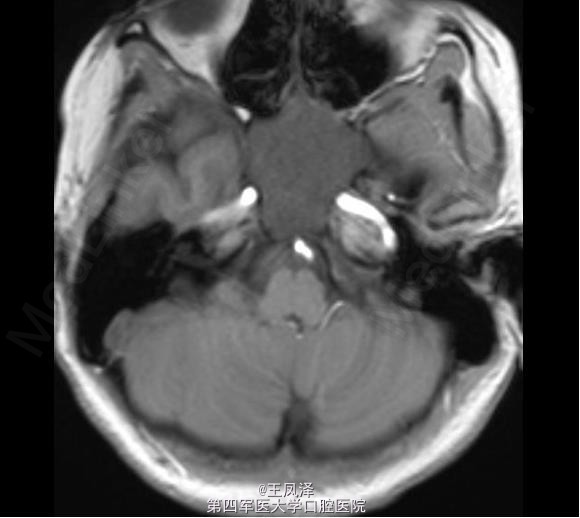

蝶窦粘液囊肿一例

女性,20 岁,在 18 个月大时诊断为自闭症和智力迟钝,目前发生多次抽搐现象,可能为癫痫发作。